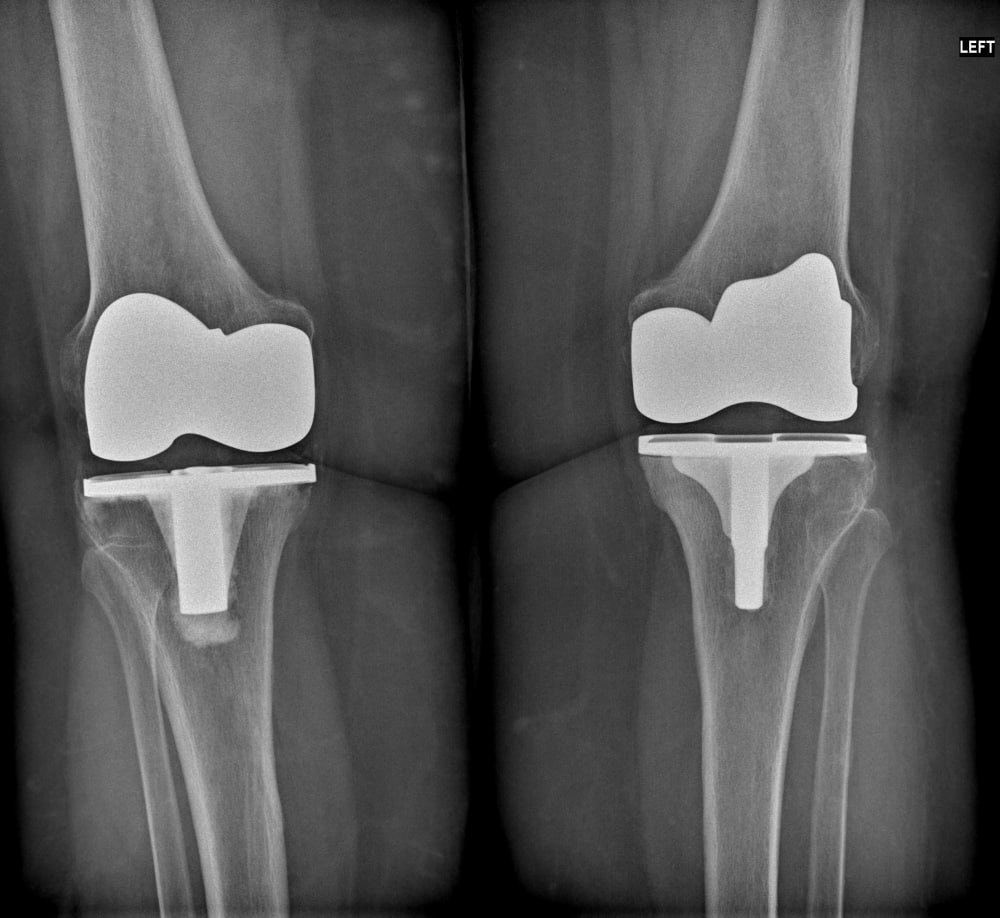

Наша пациентка 74 лет, страдающая двусторонним гонартрозом (разрушены оба коленных сустава), имела аналогичные проблемы. После замены правого коленного сустава она начала вести более подвижный образ жизни, боли уменьшились, а главное – она поняла, что из ее ситуации есть выход! Как следствие, похудела более чем на 10 кг!

5 месяцев назад мы заменили ей левый коленный сустав. Теперь она может ходить и вести нормальный образ жизни! Боли не беспокоят. Под наблюдением диетолога и эндокринолога она продолжает нормализовывать свой вес.